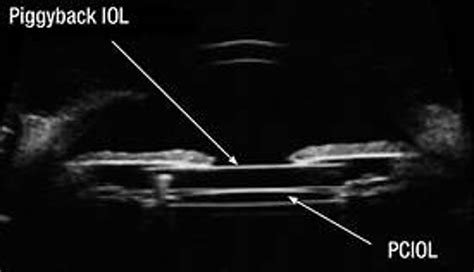

When two IOLs are implanted in an eye, it is called piggyback IOL implantation. It is usually done when patients have high refractive errors that cannot be corrected through conventional monofocal IOLs.

A piggyback IOL is an additional lens placed over an already existing IOL. It is a secondary IOL placed in front of or behind the primary IOL. It is usually done to improve vision in patients who have already undergone cataract surgery but still have some refractive errors.

A piggyback IOL is an additional IOL implanted on top of the primary IOL to fine-tune the refractive outcome. This is done when the primary IOL does not provide the correct refractive power or when it is difficult to accurately predict the post-operative refractive outcome. Piggyback IOLs can be made of different materials and shapes, and their power can be calculated using different formulas.

Piggyback IOLs consist of two lenses implanted in the eye. The first is implanted in the same position as a conventional IOL, and then a second lens is placed in front of the first. The two lenses combine to create a longer focal length than a single IOL can provide.